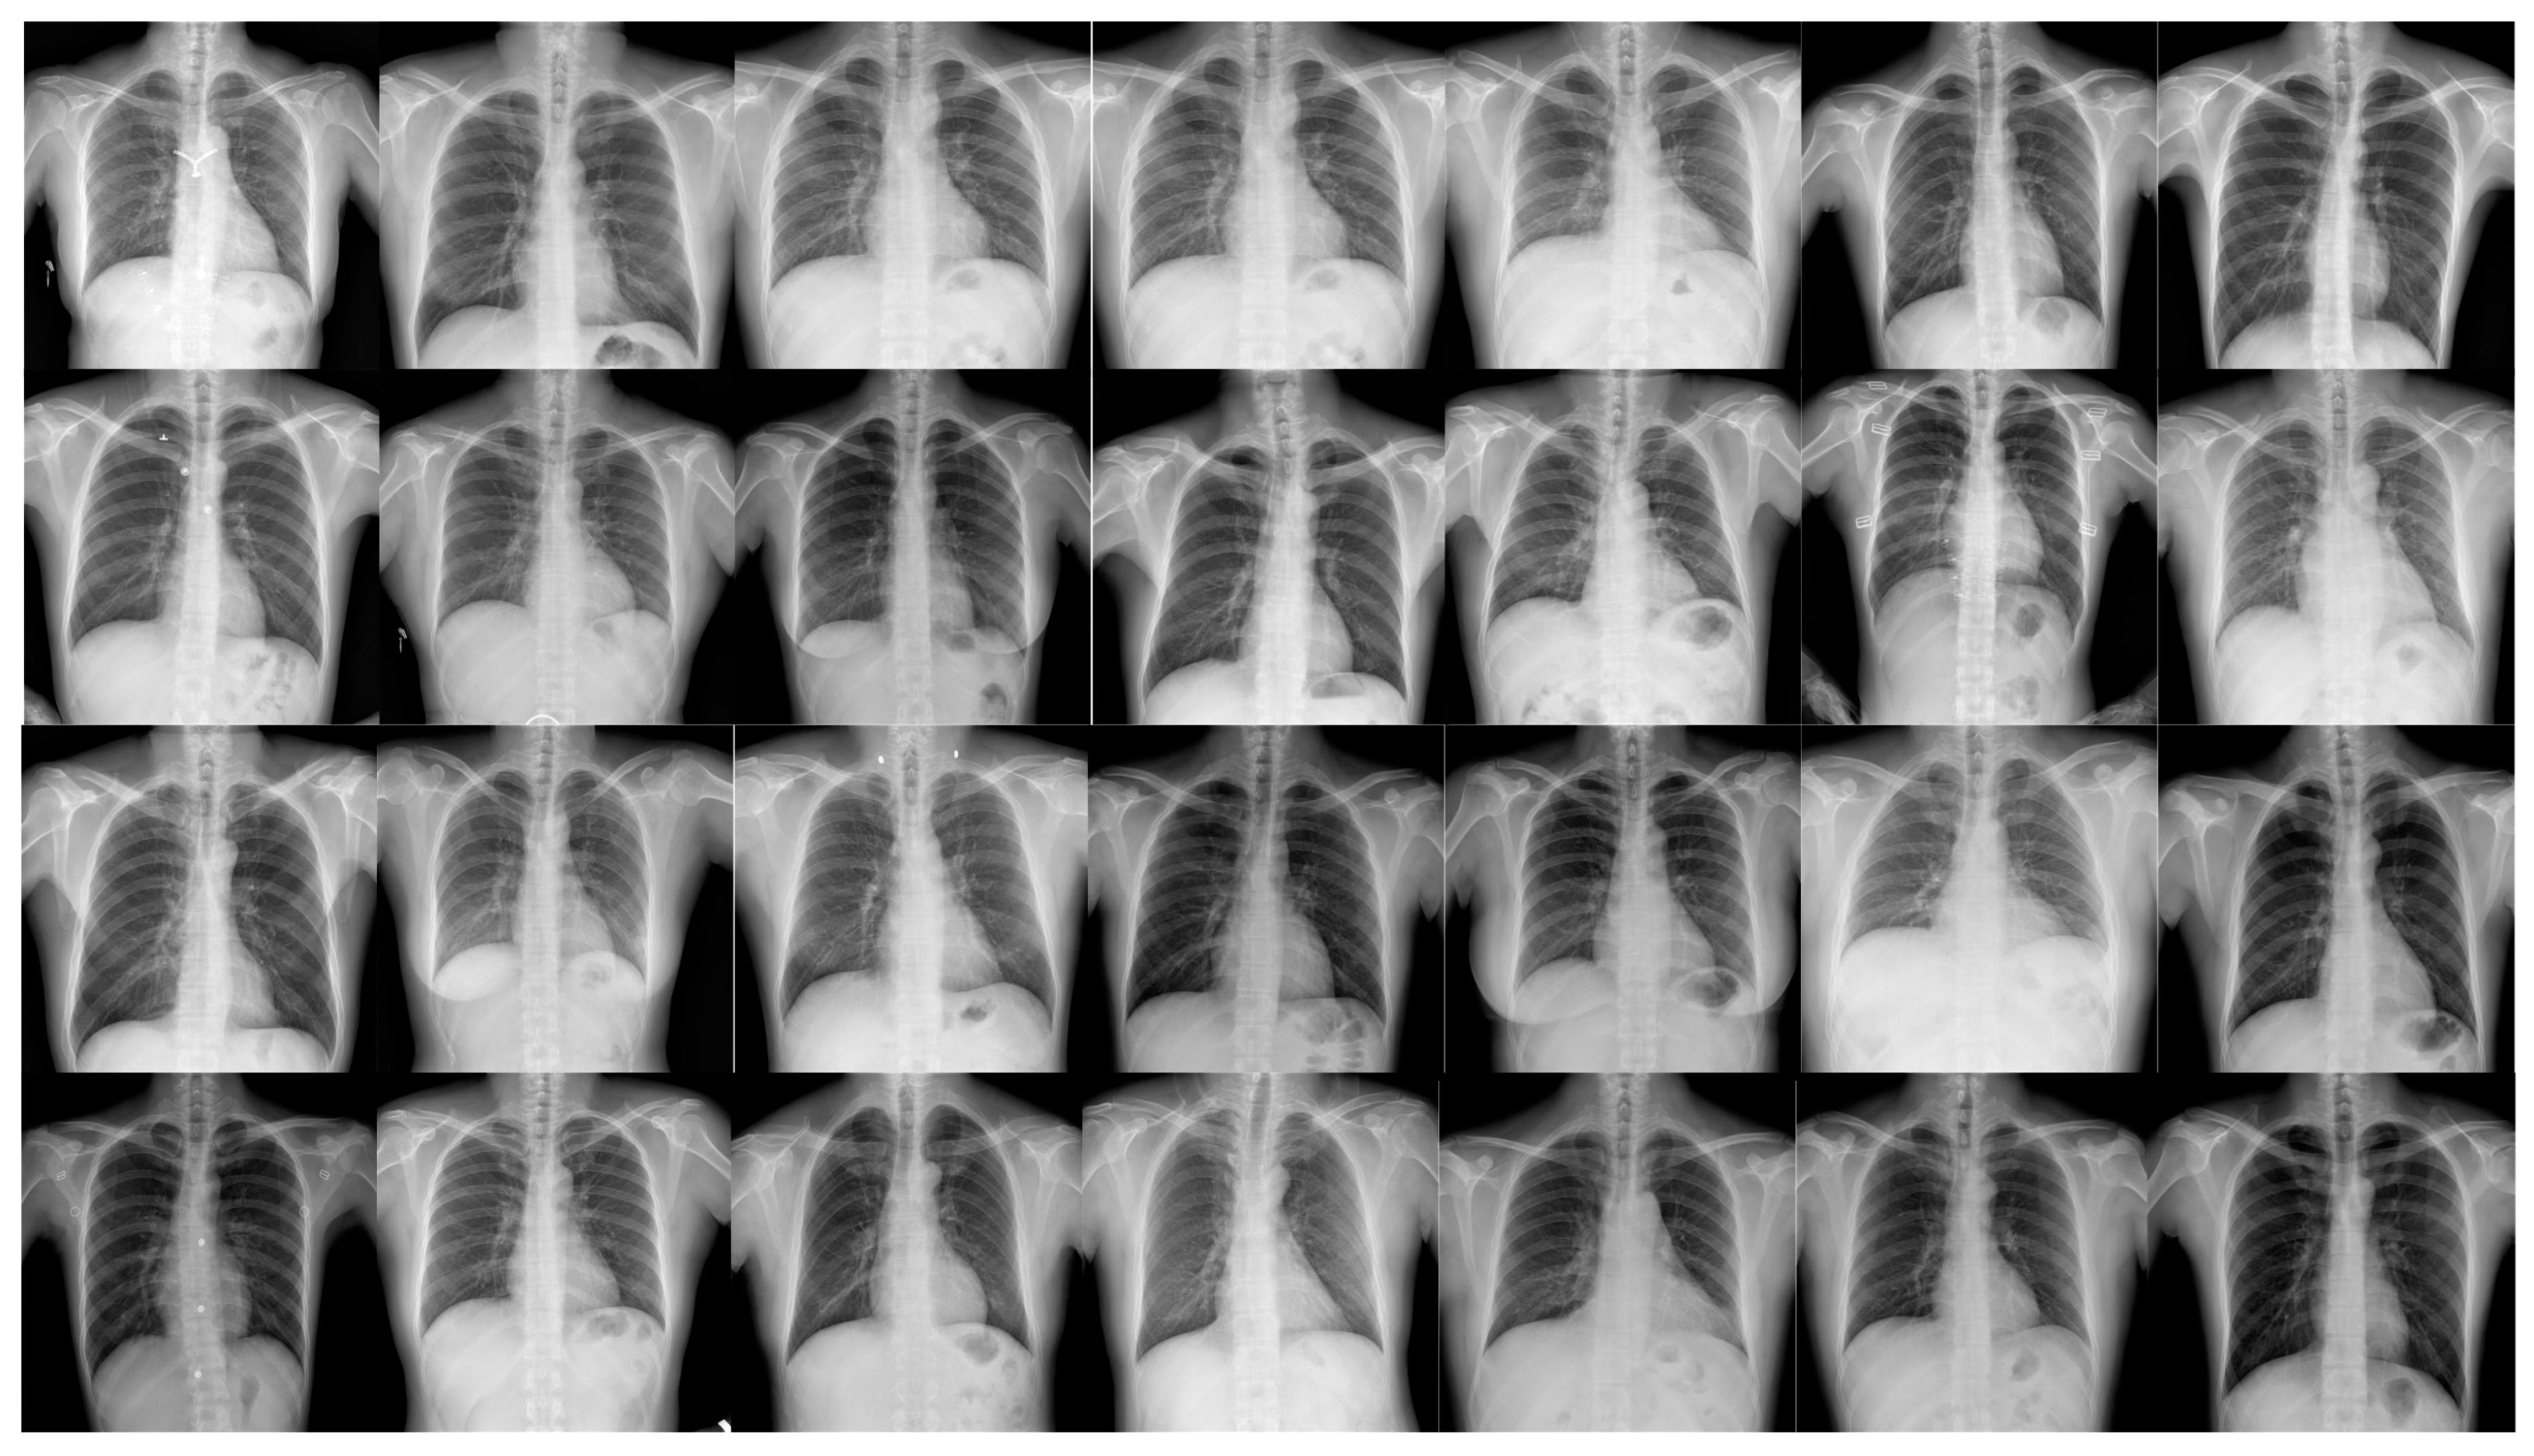

In this paper, we propose a targeted online data augmentation method. This method integrates several advanced image enhancement techniques, including Mixup and Mosaic, for comprehensive dataset preprocessing, significantly improving the model’s generalization ability and robustness [16,17,18,19].Annotated examples from the pneumonia dataset are shown in Figure 1. Specifically, the data augmentation process involved HSV transformation, translation, scaling, horizontal flipping, random cropping, zooming, and stitching [20,21]. These techniques not only effectively increase the sample size but also enhance the model’s sensitivity and adaptability in small-object detection, providing strong support for the overall optimization of model performance.

Figure 1.

Pneumonia detection dataset.